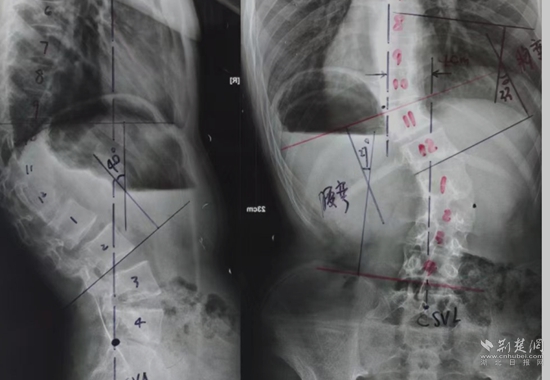

全脊柱X光檢查。通訊員 供圖

余國(guó)慶醫(yī)生檢查后發(fā)現(xiàn),這名患者全身皮膚長(zhǎng)滿(mǎn)咖啡色的斑塊和瘤狀的突起,身體極為消瘦,骨架突出后可以看到明顯的駝背、剃刀背及側(cè)彎畸形。結(jié)合隨后的全脊柱X光檢查,確診這是一例少見(jiàn)的神經(jīng)纖維瘤病性脊柱側(cè)后凸畸形患者。余醫(yī)生當(dāng)即將這名患者收住院治療。